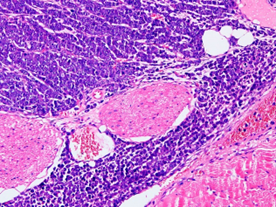

裸鼠坐骨神经肿瘤浸润模型